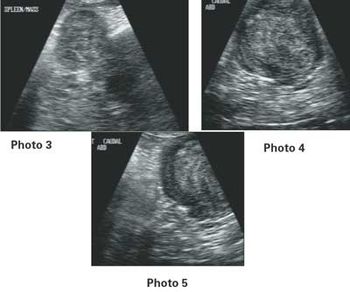

Signalment: Canine, Greyhound, 2.5 years old, female spayed, 65 lbs. Clinical history: The dog has a persistent urinary tract problem ? hematuria for at least one year according to the owner. The dog improves with antibiotics, but once finished, hematuria starts again. Therapy has included Clavamox.